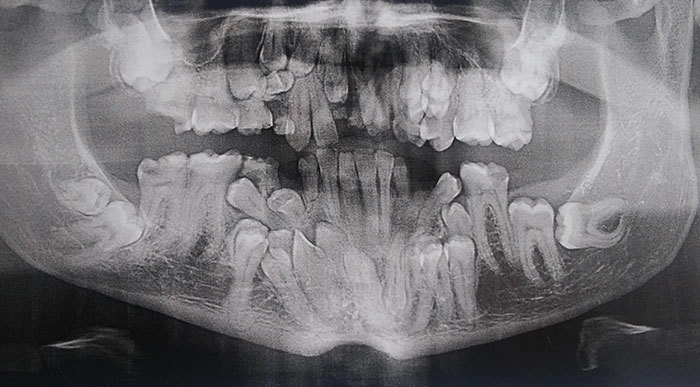

Снимок челюсти человека с клидокраниальным дизотозом (избыточное количество молочных или постоянных зубов)